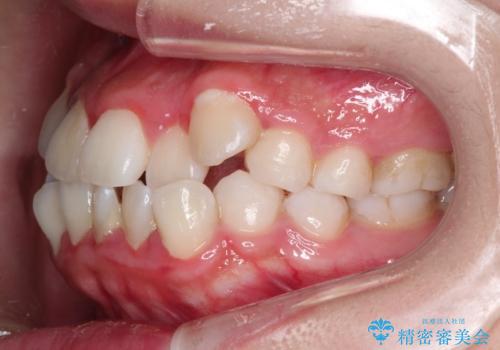

八重歯を改善!美しい口元を実現するハーフリンガル矯正

- 前歯のガタツキと口元のコンプレックスを解消するために来院されました。

ハーフリンガル矯正は、見た目を気にせずに矯正治療ができる方法です。この治療法は、八重歯や前歯のガタツキを効果的に改善します。特徴として、ワイヤーが上の歯の裏側に装着されるため、装置が外から見えません。これにより、治療中も自然な笑顔を保ちながら安心して治療を続けることができます。歯並びの悩みを持つ方にとって、非常に魅力的な選択肢です。